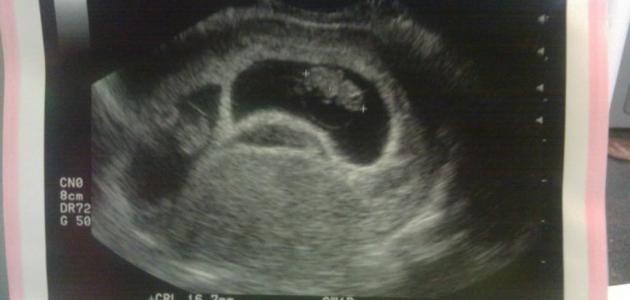

تجدر الإشارة إلى التصوير بالموجات فوق الصوتية عبر المهبل (بالإنجليزية: Transvaginal ultrasound) يكون أكثر دقة من التصوير بالموجات فوق الصوتية عبر البطن (بالإنجليزية: Abdominal ultrasound) في مراحل الحمل المبكرة، وفي العادة يكون ظهور الكيس الحملي (بالإنجليزية: Gestational sac) هو أول علامات الحمل التي تظهر على جهاز الموجات فوق الصوتية (بالإنجليزية: Ultrasound)، حيث يمكن أن يظهر بعد مرور أول 3 أسابيع من الحمل، ويُقدّر معدل قطر كيس الحمل في هذا الوقت بحوالي 2-3 مليمتر، وبعد مرور ما يُقارب خمسة أسابيع ونصف من الحمل يظهر الكيس المُحيّ (بالإنجليزية: Yolk sac) داخل كيس الحمل، ومما ينبغي التنويه إليه أنّ كيس الحمل يظهر في التصوير بالموجات الصوتية عبر البطن عندما ترتفع مستويات هرمون موجهة الغدد التناسلية المشيمائية (بالإنجليزية: Hُuman chorionic gonadotropin) المعروف بهرمون الحمل وتصل إلى ما يقارب 1500 -2000 وحدة دولية/لتر،[٢] وهنا نُشير إلى أنّ هرمون موجهة الغدد التناسلية المشيمائية يوجد في الدم منذ بداية حدوث الانغراس (بالإنجليزية: Implantation) للبويضة المخصبة أو الجنين في جدار الرحم،[٣] ويمكن الكشف عن هذا الهرمون من خلال إجراء تحاليل واختبارات الحمل، وقد تكشف بعض تحاليل الحمل عن هذا الهرمون في فترة مبكرة بعد مرور حوالي 7 أيام فقط من الإباضة (بالإنجليزية: Ovulation).[٤]